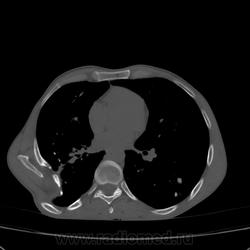

Состояние после торакопластики.

Молодой человек 30 лет, в 04 году выявлен фиброзно-кавернозный ТБ, в течение 12 месяцев лечился в стационаре, прооперирован-5реберная торакопластика справа, через 3 года переведен в 3ГДУ, в 10году снят с ДУ по излечению. Пришел провериться по ухудшению состояния. На КТ легких данных за рецидив ТБ, вроде нет. С " торакопластикой" был единственным пациентом на учете.

Состояние после правосторонней 5-реберной торакопластики по поводу ФКТ.Грубые остаточные изменения:поликистоз,буллезно-дистрофические изменения,плевропневмоцирроз правого легкого..Нет ли  мелкоочаговой диссеминации в обоих легких?Нужен Rархив.(ПТД).

Нет, это кальцинаты и более плотные уже. Архив только пленочный, 8 лет назад "цифры" не было. Можно и пленку перефотать...

Редко встречалось, а на КТ вижу впервые, спасибо за случай! На показанных изображениях отсевов не увидела.